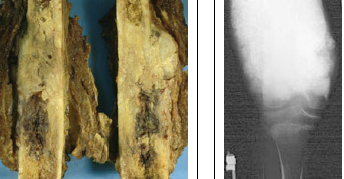

25

Pathology

Chondrosarcoma malignant, cartilage-producing tumor 30-50 years, extremely rare in children; bones of trunk (pelvis), femur, and humerus

26

Pathology?

Chondrosarcoma large, lobulated, ill-defined lesion; moderately cellular, atypia